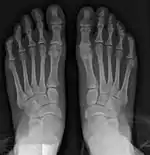

![]() Fig. 8a. Painful hallux valgus and metatarsus primus varus deformity recurrence of left foot after osteotomy surgery | |

- For recurrence correction after osteotomy procedure (Fig. 8)

Late deformity recurrence can happen after osteotomy (bone-breaking) procedures because osteotomy surgeries do not specifically stabilize first metatarsal bone.